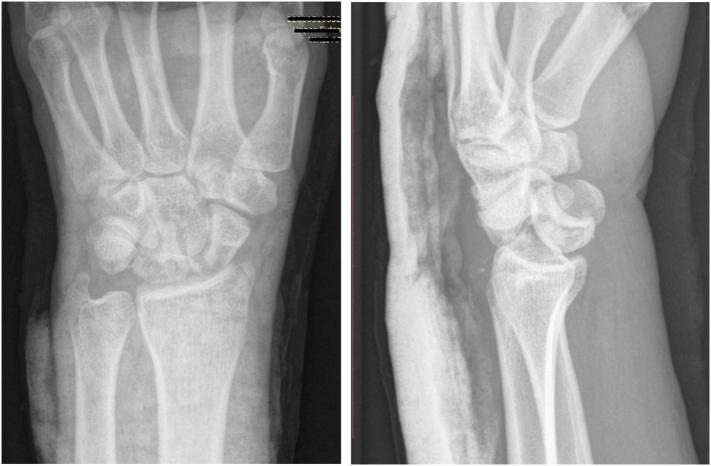

An unusual wrist injury in a parkour-athlete: Transstyloid, transscaphoid, transtriquetral perilunate dislocation.

Perilunate dislocations are uncommon high energy injuries. The combination of fractures resulting in a trans-styloid, trans-scaphoid, and trans-triquetral perilunate fracture dislocation is extremely rare. We describe a 20 year old male who suffered this injury after a fall from height while parkouring. He underwent open reduction and internal fixation with ligamentous repair and carpal tunnel decompression. After 3 months, he was noted to have a radiographic evidence of scapholunate dissociation and he returned to the operative room for definitive fixation. Despite this complication, the final functional outcome 6 months after the second surgery was satisfying.